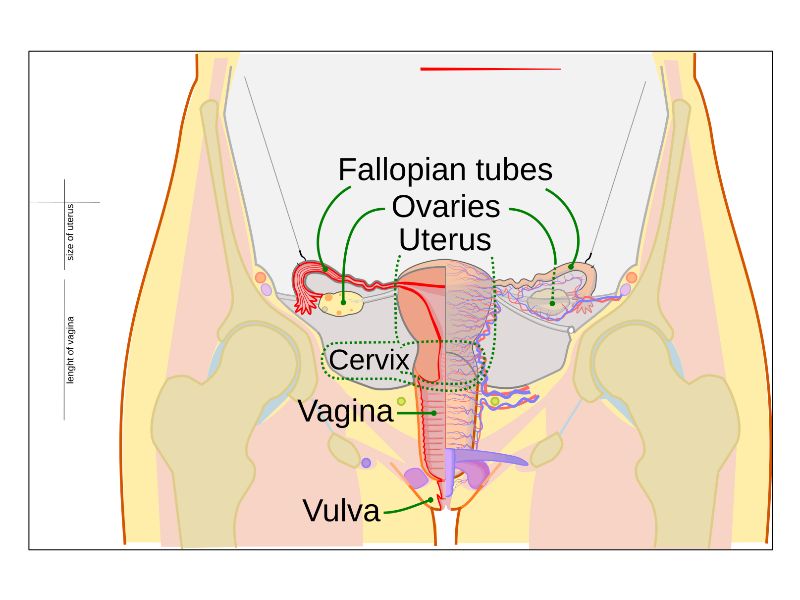

Ovaries

Tuba uterina

Uterus

Vagina